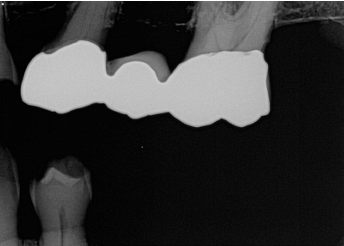

What is the problem with this DEVELOPER CUT-OFF X-ray?

Appears with a straight white border, Undeveloped portion of film caused by low level of developer

How would you resolve this DEVELOPER CUT-OFF X-ray?

Check developer level before processing and add solution if needed